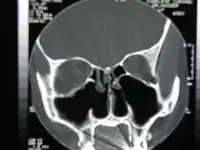

La turbinectomie est une intervention chirurgicale destinée à retirer en totalité ou partiellement les cornets du nez. C'est une intervention qui se pratique généralement dans le cabinet d'un oto-rhino-laryngologiste (ORL) à l'aide d'un laser CO2. Elle est recommandée par le praticien lorsque le patient se plaint de gênes respiratoires chroniques.

Le terme turbinoplastie réfère au retrait partiel des cornets du nez[1].